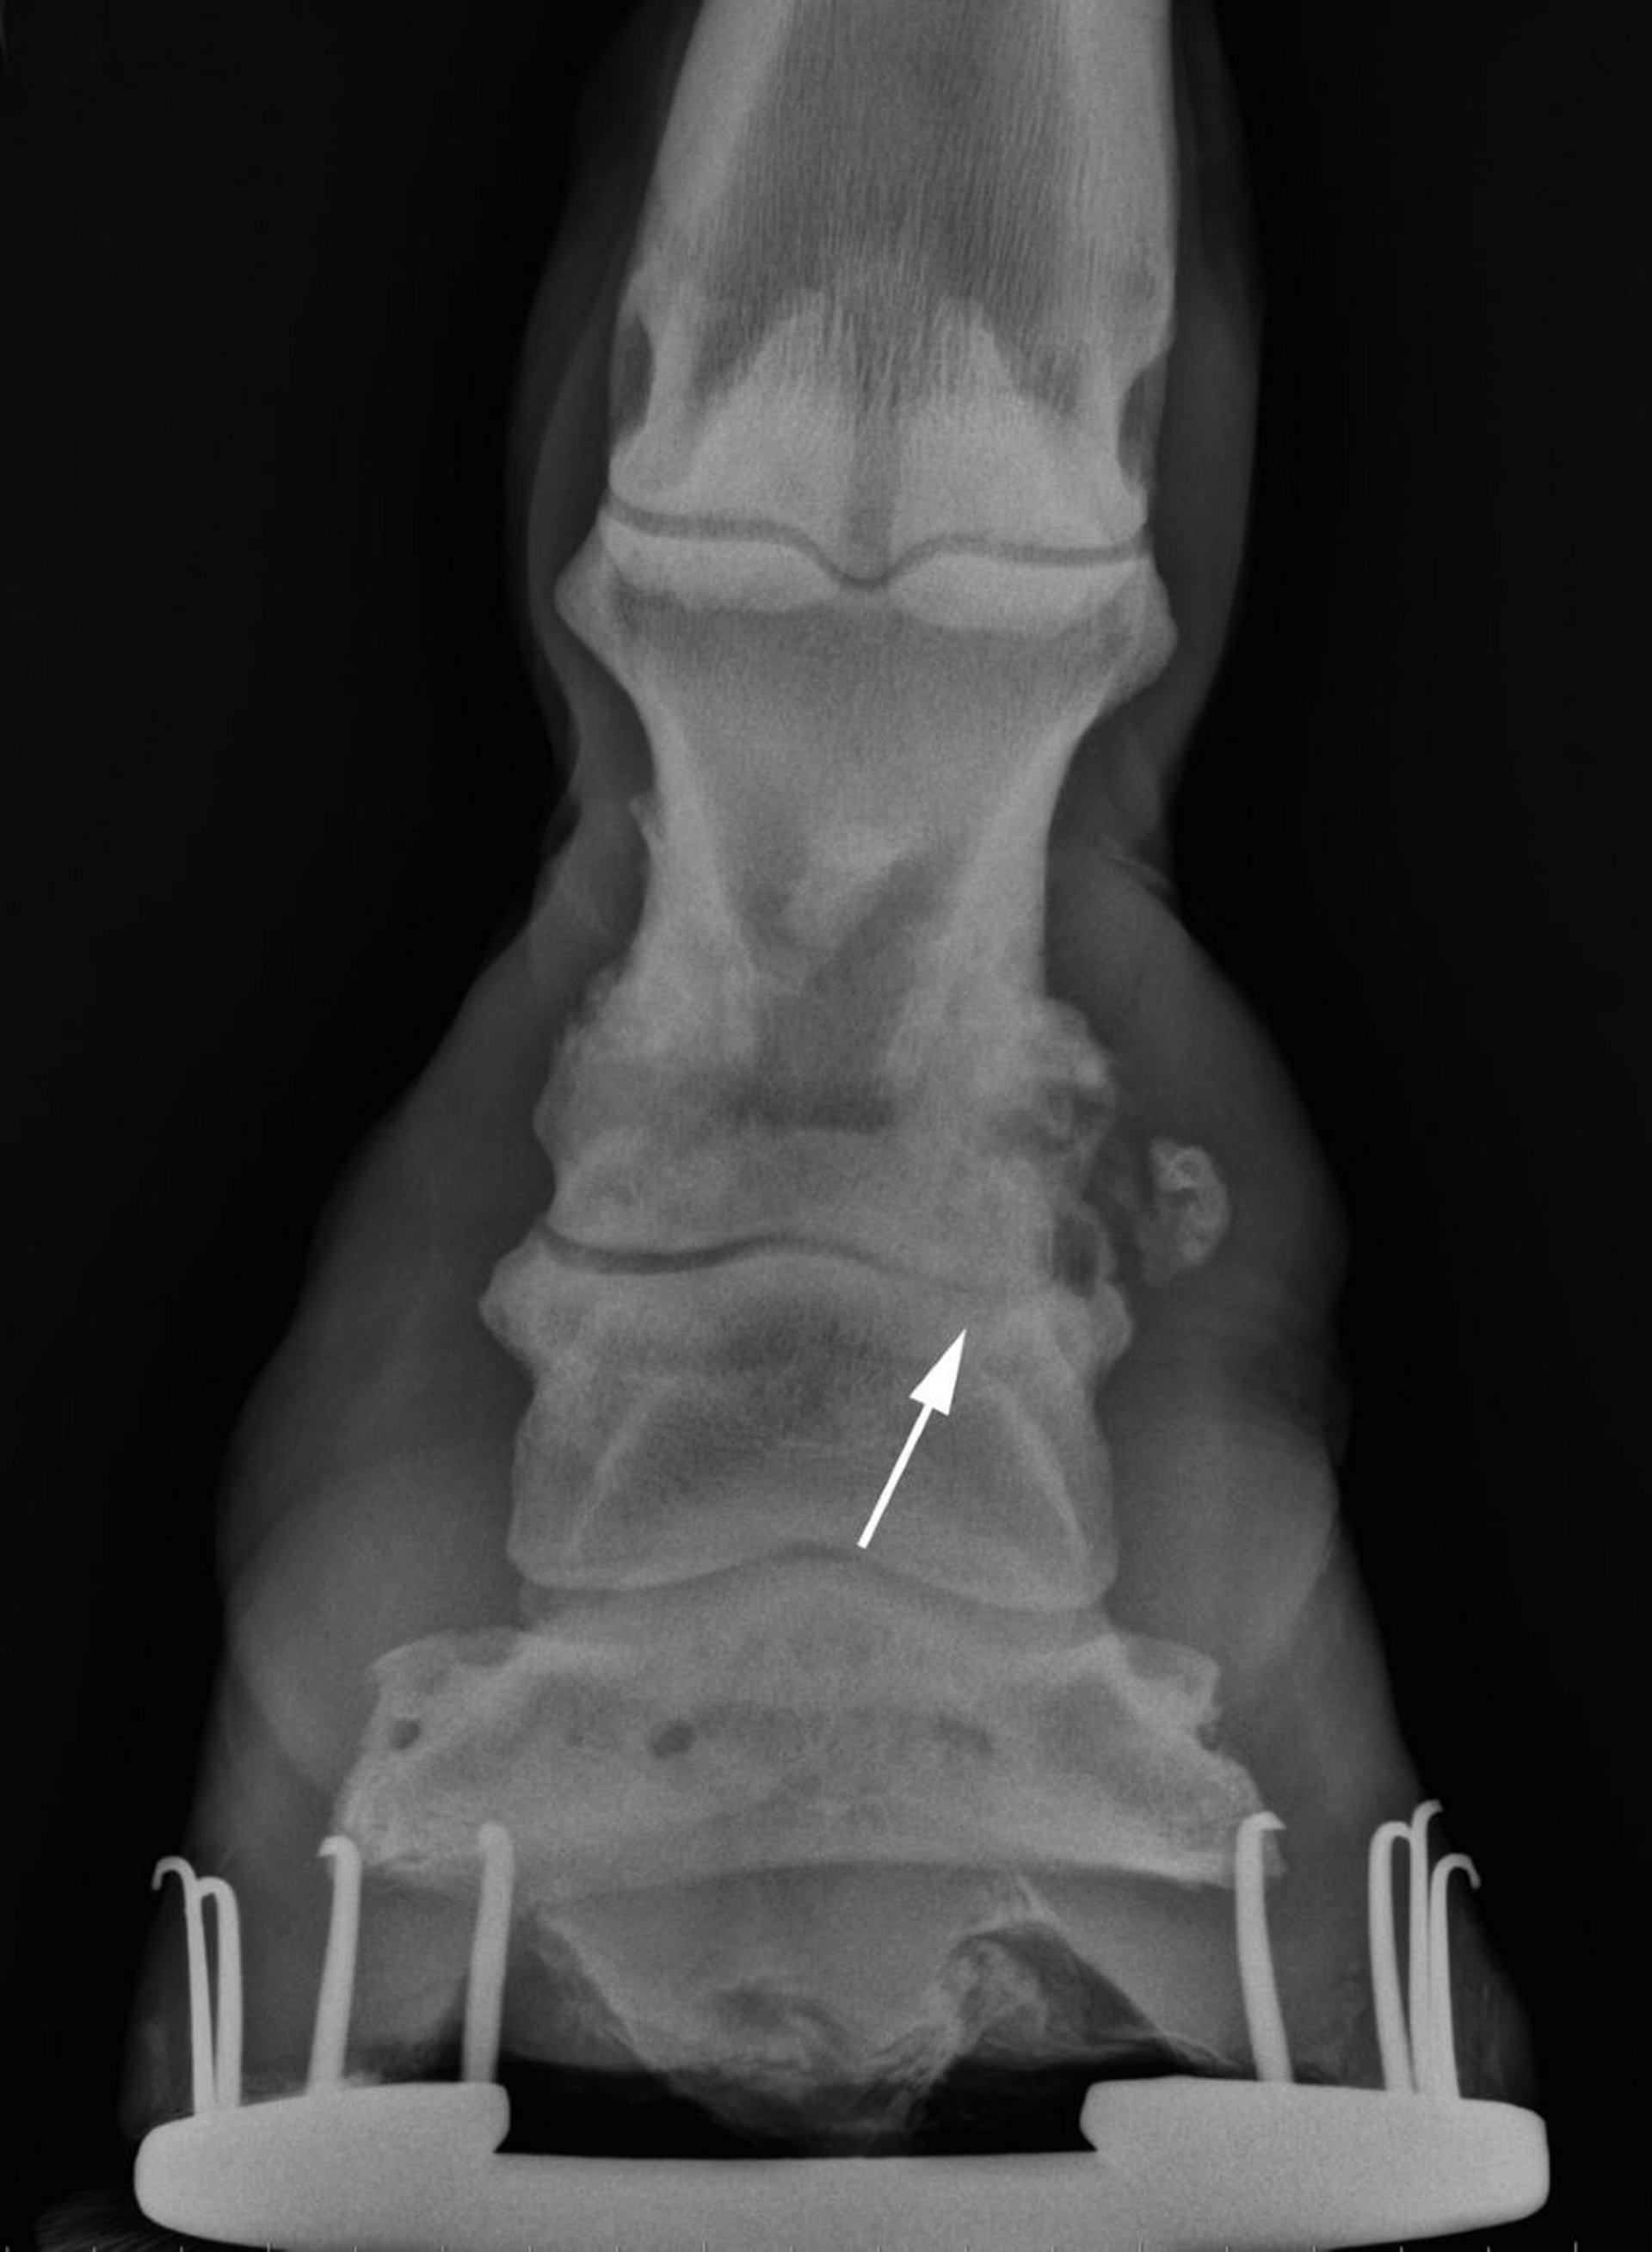

Radiografía de artrosis en la articulación interfalángica proximal en caballos

Imagen radiográfica que muestra artrosis crónica marcada en la articulación interfalángica proximal con una probable fractura previa por avulsión de la porción distolateral de la P2. Se observan osteólisis y pérdida del espacio articular en el aspecto medial de la articulación (flecha).

Cortesía del Dr. Matthew T. Brokken.